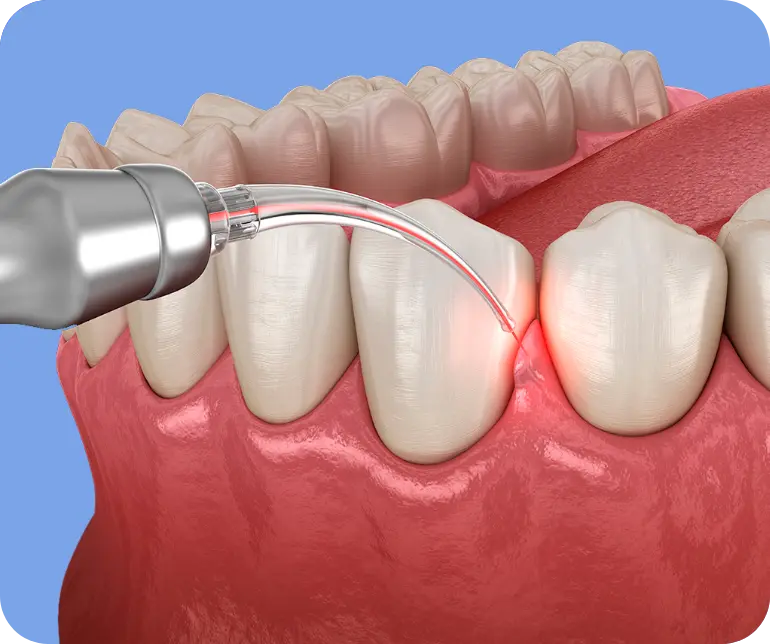

Interventi indolore e non invasivi?

Scopri il Laser a Diodo

Il nostro studio è equipaggiato con il laser a diodo, una rivoluzione tecnologica che permette interventi indolori e minimamente invasivi.

Dalle frenulectomie per migliorare la mobilità di lingua e labbra alla desensibilizzazione dei denti sensibili, il laser offre risultati superiori con tempi di recupero ridotti.